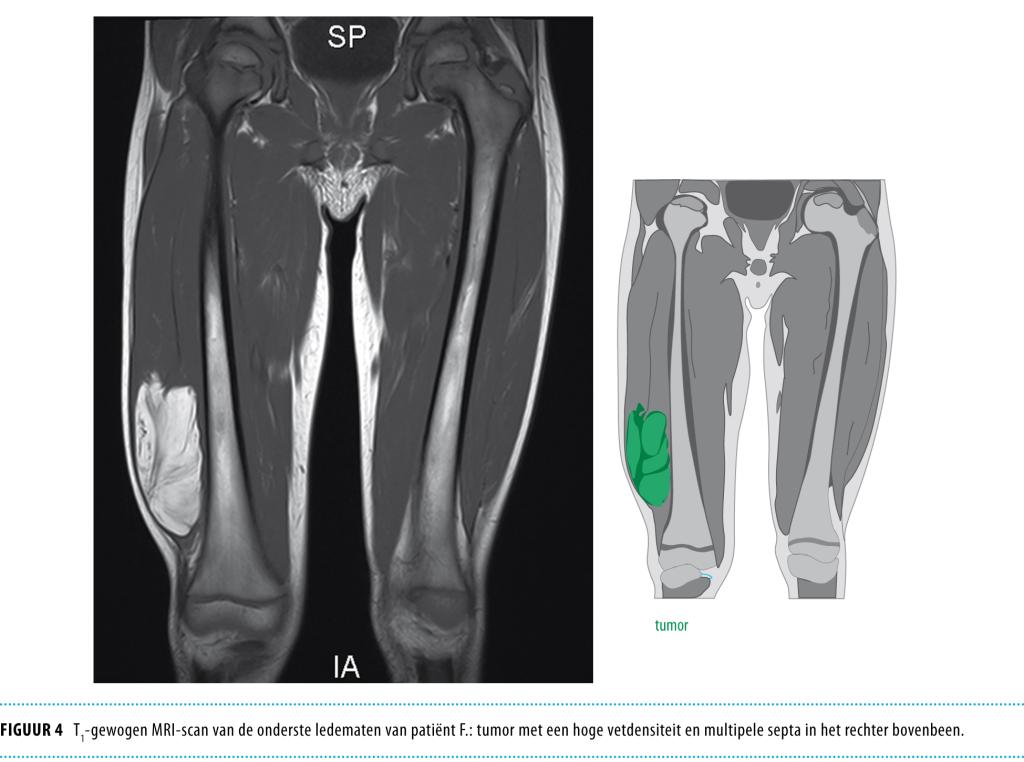

Patiënt B, een meisje van 15 maanden oud, werd gezien vanwege een harde, niet pijnlijke massa aan de dorsale zijde van het rechter bovenbeen. Deze massa was door de ouders enkele dagen eerder voor het eerst opgemerkt. Een CT-scan toonde een tumor met een hoge vetdensiteit en meerdere septa (figuur 2), sterk verdacht voor een lipoblastoom. De tumor werd chirurgisch volledig verwijderd. Pathologisch onderzoek toonde vetweefsel met een grote variatie in vetceldiameter en een duidelijk lobulaire opbouw. Tussen de vetcellen waren talrijke myxoïde velden herkenbaar. De waarschijnlijkheidsdiagnose ‘lipoblastoom’ werd gesteld. Cytogenetisch onderzoek toonde een polysomie van chromosoom 8: 49,XX,+8,+8,+8, wat de diagnose ‘lipoblastoom’ bevestigde. Na een follow-up van 3 jaar was er geen recidief.

Figuur 2